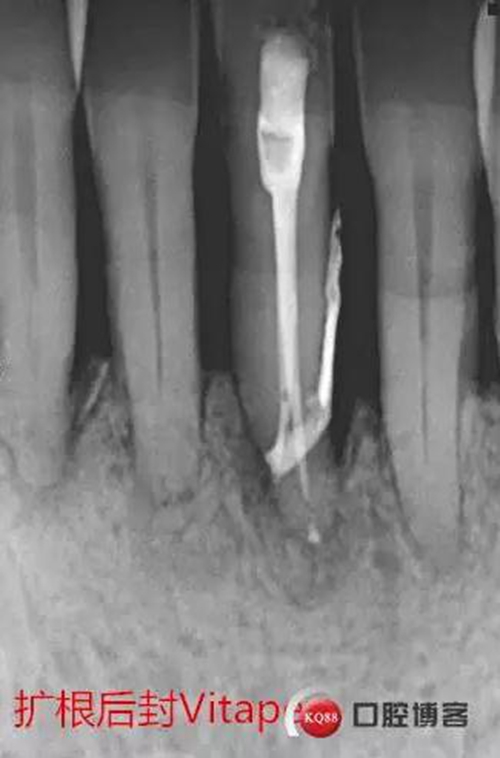

處理:31去暫封,手用銼疏通根管,沖洗,機擴至04錐度30#,超聲蕩洗,封維塔,拍片。

由于兩次根管內(nèi)封藥后,頰根處均有多余藥物擠出根尖孔,考慮根尖孔處受破壞或根尖周炎癥導致牙周膜疏松,故封藥兩周后復診。